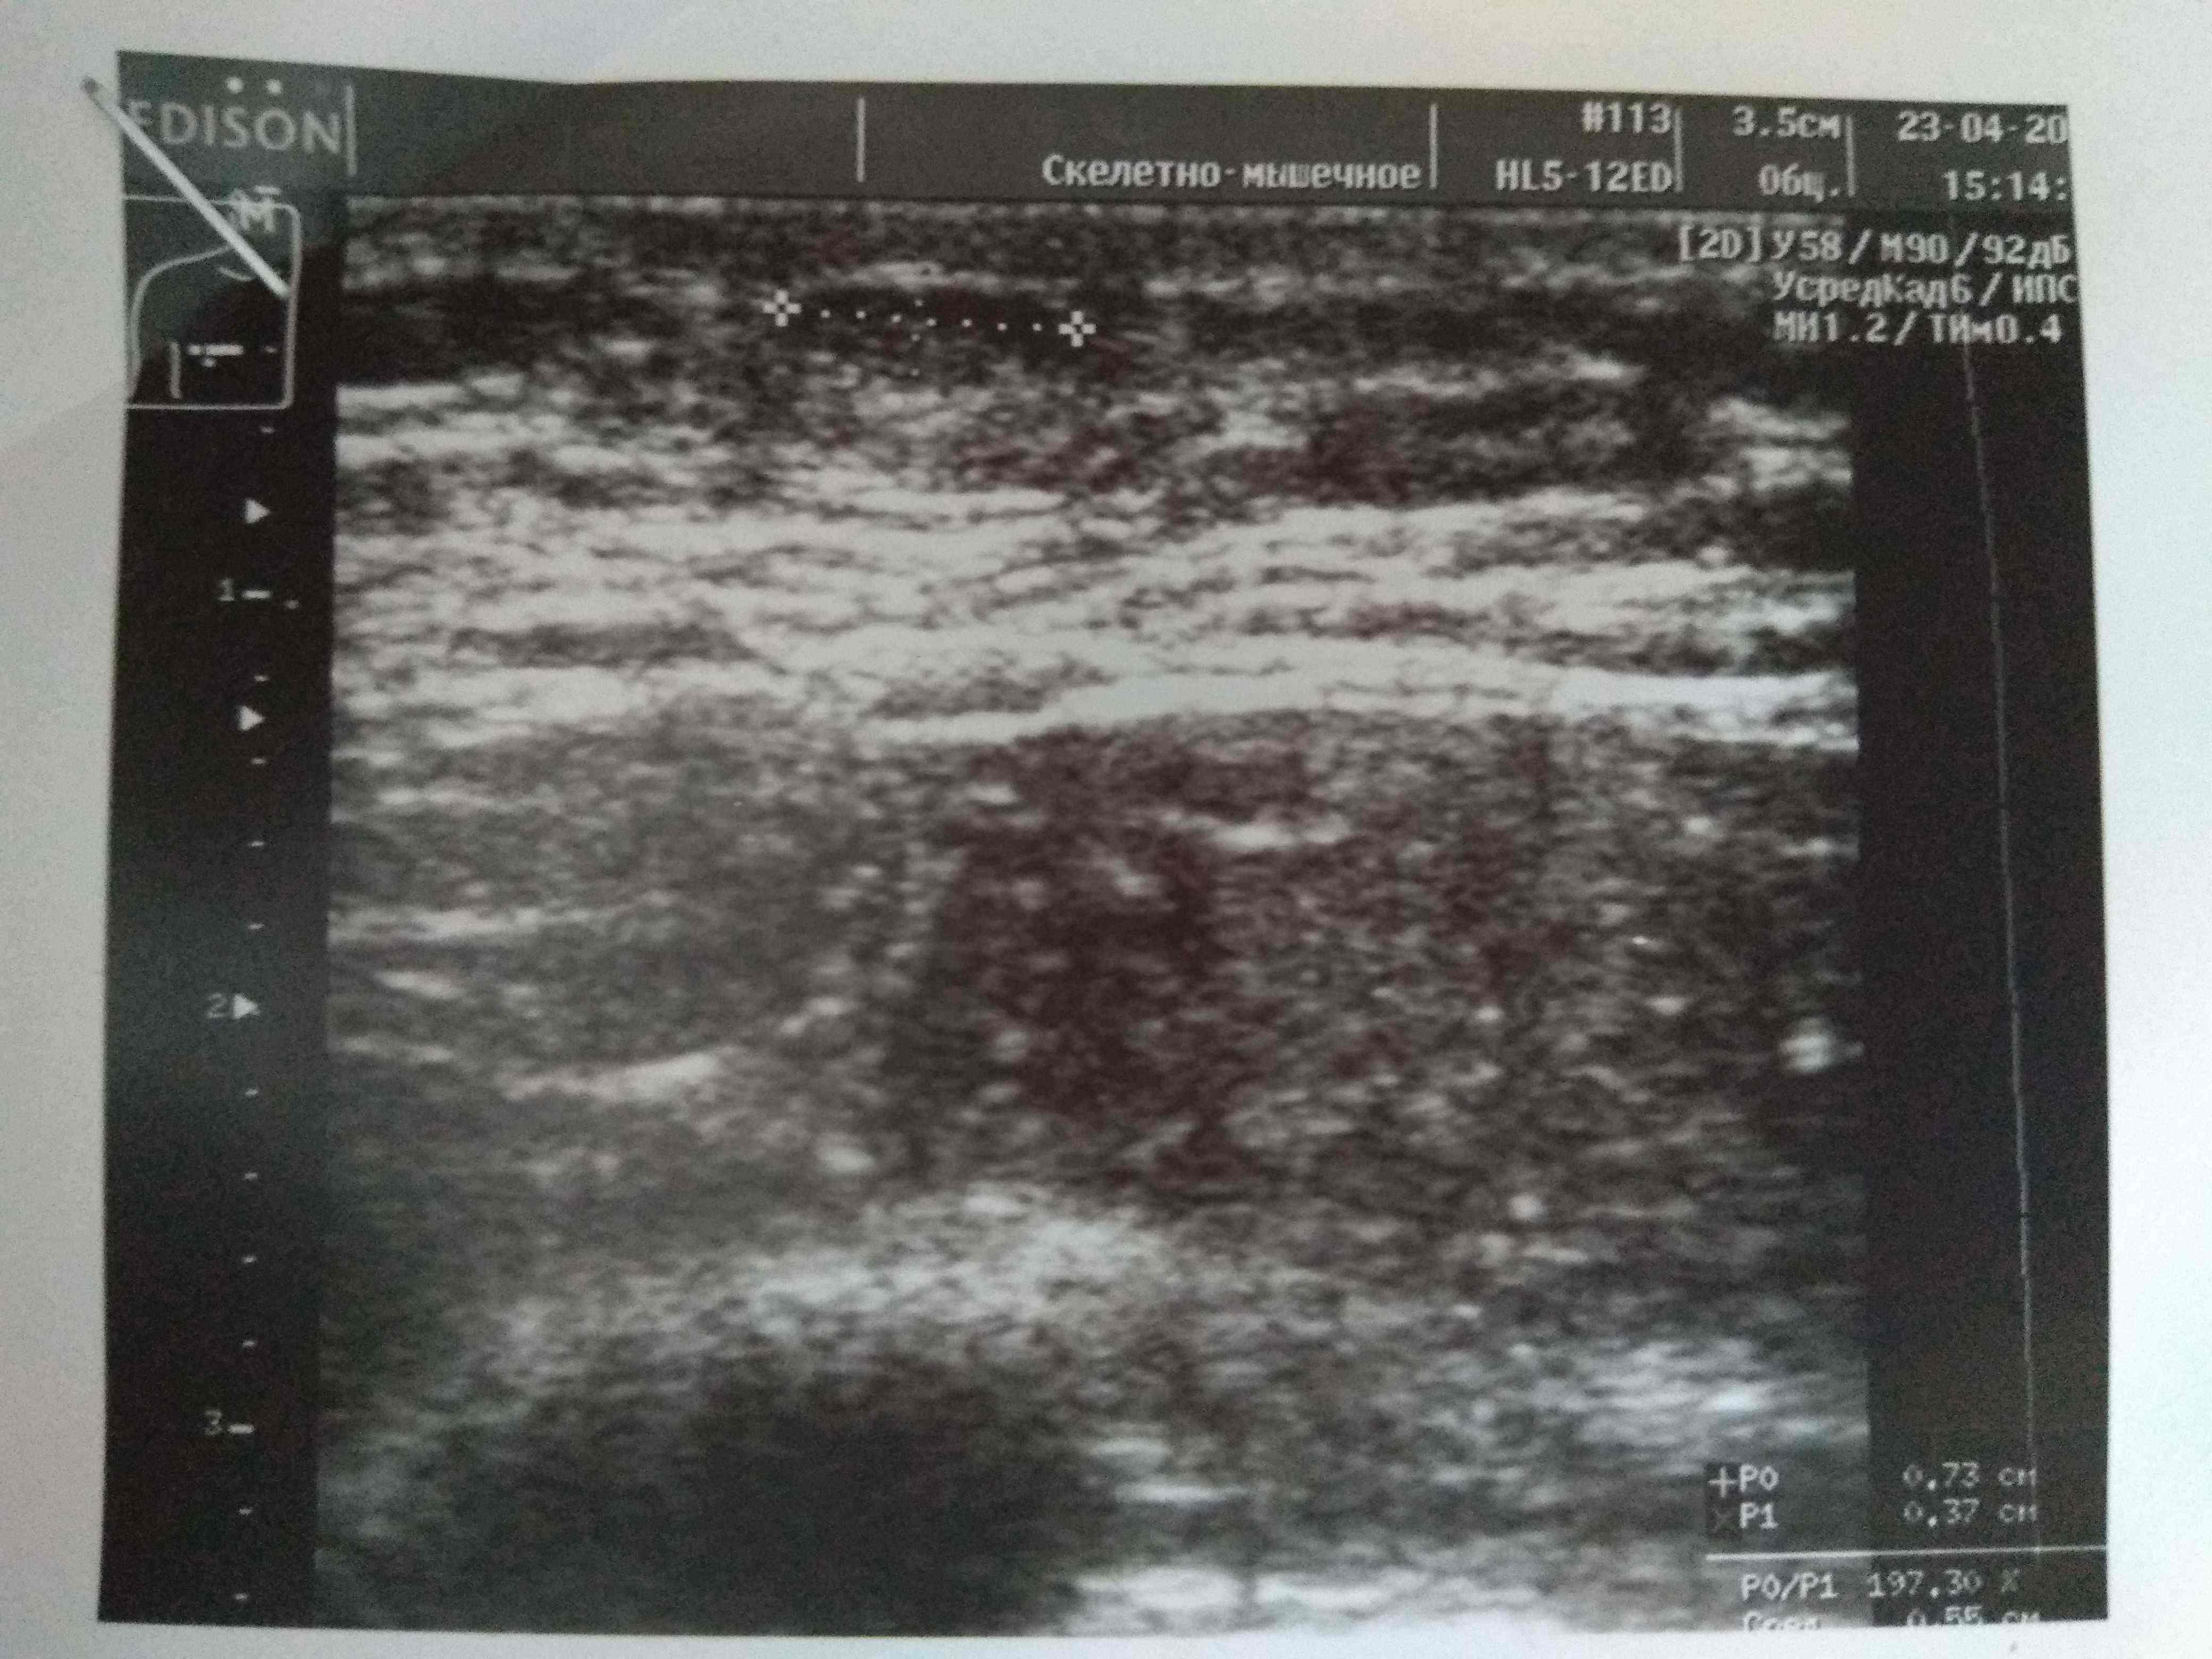

Парни всем доброго вечера! Недавно поднимали вопрос об уплотнении в области сосков на курсах с декой. Суть вопроса что анализы постоянно контролирую как строгая мамка бережет девственность дочки старшеклассницы и они находятся в референсах а уплотнение есть и как будто бы немного растет. Сгонял на УЗИ чтобы расставить все на свои места. В моем случае оно меня порадовало. Думаю что это не единичный случай поэтому и выкладываю инфу сюда. В моем случае гино и не пахло. Имеется небольшое уплотнение состоящее из фиброзно-жировой ткани. Всем здоровья и удачи:swag:

Всем привет. Был курс нанфинил100+проп100. Набухли сиськи. Е2 и пролоктин в норме. PartyKill посоветовал сделать УЗИ .Результат: Эхо-признаки двусторонней геникомастии. Ну врачи привыкли всё драматизировать и слегка преувеличивать. Но лечиться всё равно надо. Посоветуйте братья . До этого проблем с гино небыло.Может эта реакция на нанфинил такая? (Юзал первый раз)Хотя дека прошлым курсом нормально так вкатила.Стаж 4 года, ну разумеется с отдыхом , ПКТ, сдачей анализов. Всё по фэн-шую, всё как мы любим.Сейчас идёт мост , энка250 . Хотелось бы подлечиться а с июня снова в бой )) Выручайте

Посмотреть вложение 14714 Всем привет. Был курс нанфинил100+проп100. Набухли сиськи. Е2 и пролоктин в норме. PartyKill посоветовал сделать УЗИ .Результат: Эхо-признаки двусторонней геникомастии. Ну врачи привыкли всё драматизировать и слегка преувеличивать. Ну лечиться всё равно надо. Посоветуйте братья . До этого проблем с гино небыло.Может эта реакция на нанфинил такая? (Юзал первый раз)Хотя дека прошлым курсом нормально так вкатила.Стаж 4 года, ну разумеется с отдыхом , ПКТ, сдачей анализов. Всё по фэн-шую, всё как мы любим.Сейчас идёт мост , энка250 . Хотелось бы подлечиться а с июня снова в бой )) Выручайте

Ну да, железа увеличина.

Давай тогда сделаем как советовал Дон, фарестон по 60 в день на месяц, после месяца сделать УЗИ повторно и посмотреть на динамику